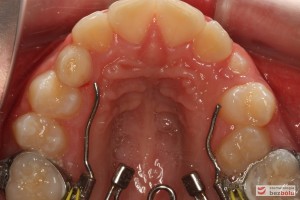

Rodzice zgłosili się z pacjentem celem rutynowej kontroli ortodontycznej. Wykonano OPG i po analizie modeli diagnostycznych stwierdzono brak miejsca dla wyrzynania dolnej prawej piątki stałej oraz zwężenie szczęki wraz z rotacją górnych zębów szóstych. W łuku górnym w pierwszym etapie leczenia zastosowano Rotator, celem odrotowania 6-tek stałych oraz ekspansji łuku w wymiarze poprzecznym. Następnie zamontowano aparat stały metalowy do uszeregowania zębów w łuku. W łuku dolnym miejsce odtwarzano stosując aparat stały i odpowiednią mechanikę leczenia. Leczenie aktywne trwało 3,5 roku, po czym zastosowano terapię retencyjną (retainer stały w żuchwie oraz Płytkę Hawley’a w szczęce).